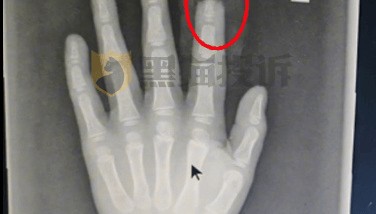

据媒体报道,今年1月,惠州陈先生一家驾驶小鹏X9出行,5岁儿子使用娱乐屏时,左手食指被伸缩支架夹住,...